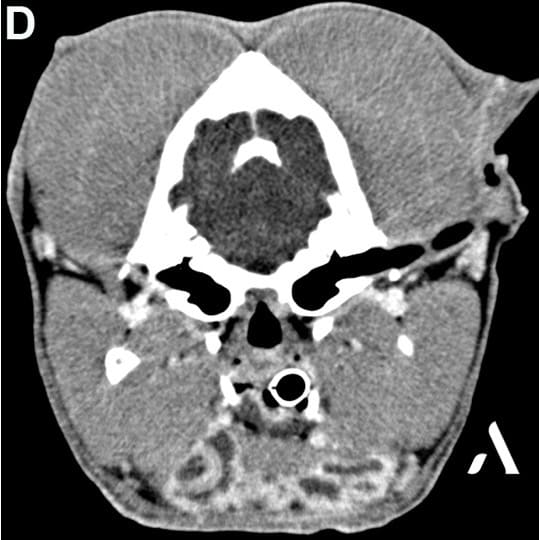

Imagerie

Un service imagerie toujours encadré par un spécialiste tout au long de l’année.